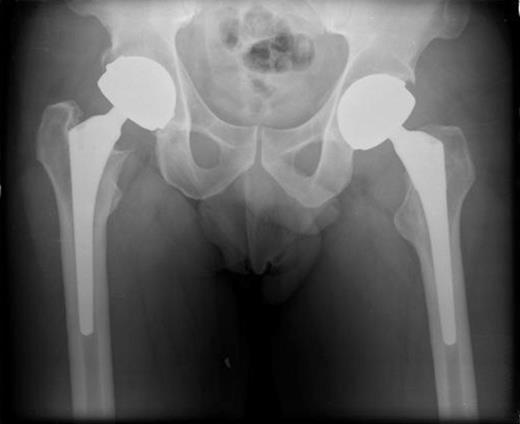

A 49 year old male patient presented to the medical admissions unit with a one week history of left hip and thigh painful swelling. The only past medical history was bilateral metal on metal total hip replacements four years prior, the indication osteoarthritis (figure 1). The patient had no problems regarding the hips since surgery.

AP Pelvis radiograph demonstrating bilateral metal on metal total hip replacements